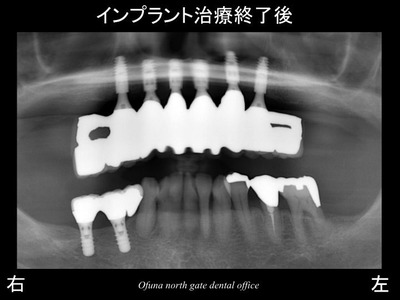

以下は、治療終了後です。

このようなケースは、治療後も綿密なケアーを行っていくことが重要です。

使用したインプラントは、アンキロス インプラント です。

前歯部に適したインプラント(プラットホーム・スイッチング) となっています。